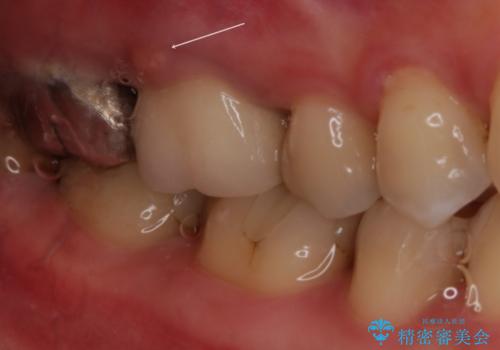

- 左上4番と左上6番が欠損しており、欠損部にはさまれた左上5番が後ろ側に倒れている状態で来院されました。

左上4番はインプラント、左上6番はブリッジにて治療することとなりましたが、左上5番が傾いているのでこのままではインプラント正しい位置に入れにくく、かぶせ物が正常な形態で装着できなくなり、ブリッジも装着が困難となります。

そこで、部分矯正をして左上5番を正しい位置に戻してからインプラント・ブリッジ治療をしていくこととなりました。